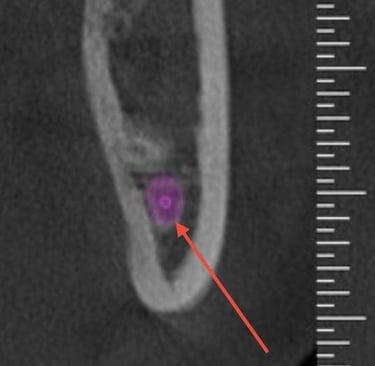

O planejamento da cirurgia dos dentes do siso normalmente é realizado por meio de tomografias computadorizadas. Elas permitem visualizar com precisão a localização do canal mandibular (seta), cuja lesão durante a cirurgia pode causar complicações neurossensoriais e hemorragias, reforçando a importância de um bom planejamento cirúrgico.